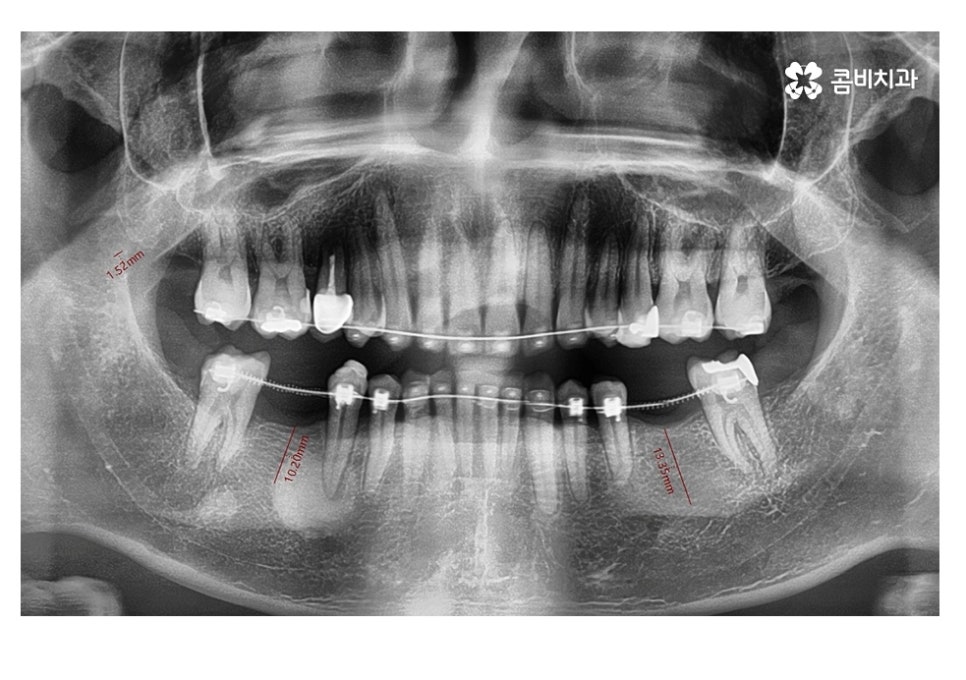

위 사례 이미지에서 보시는 것과 같이 불규칙한 치열 외에도

치아 사이가 벌어져 있으면 심미성 뿐 아니라

음식물이 치아 사이에 끼기 쉽기 때문에 충치, 잇몸질환이

발생하기 쉬울 수 있어요.

보통 임플란트와 교정을 같이 해야 하는 케이스에는

교정이 끝나기 약 6개월 전에 치료를 하게 되는 경우가 많은데

임플란트 식립 후 뼈가 완전히 굳고 치료를

마무리하기까지 보통 4~5개월 정도 걸리기 때문에

발치와 임플란트의 시술 그리고 교정이 비슷한 시기에

끝날 수 있도록 치료 계획을 세우고 있어요.